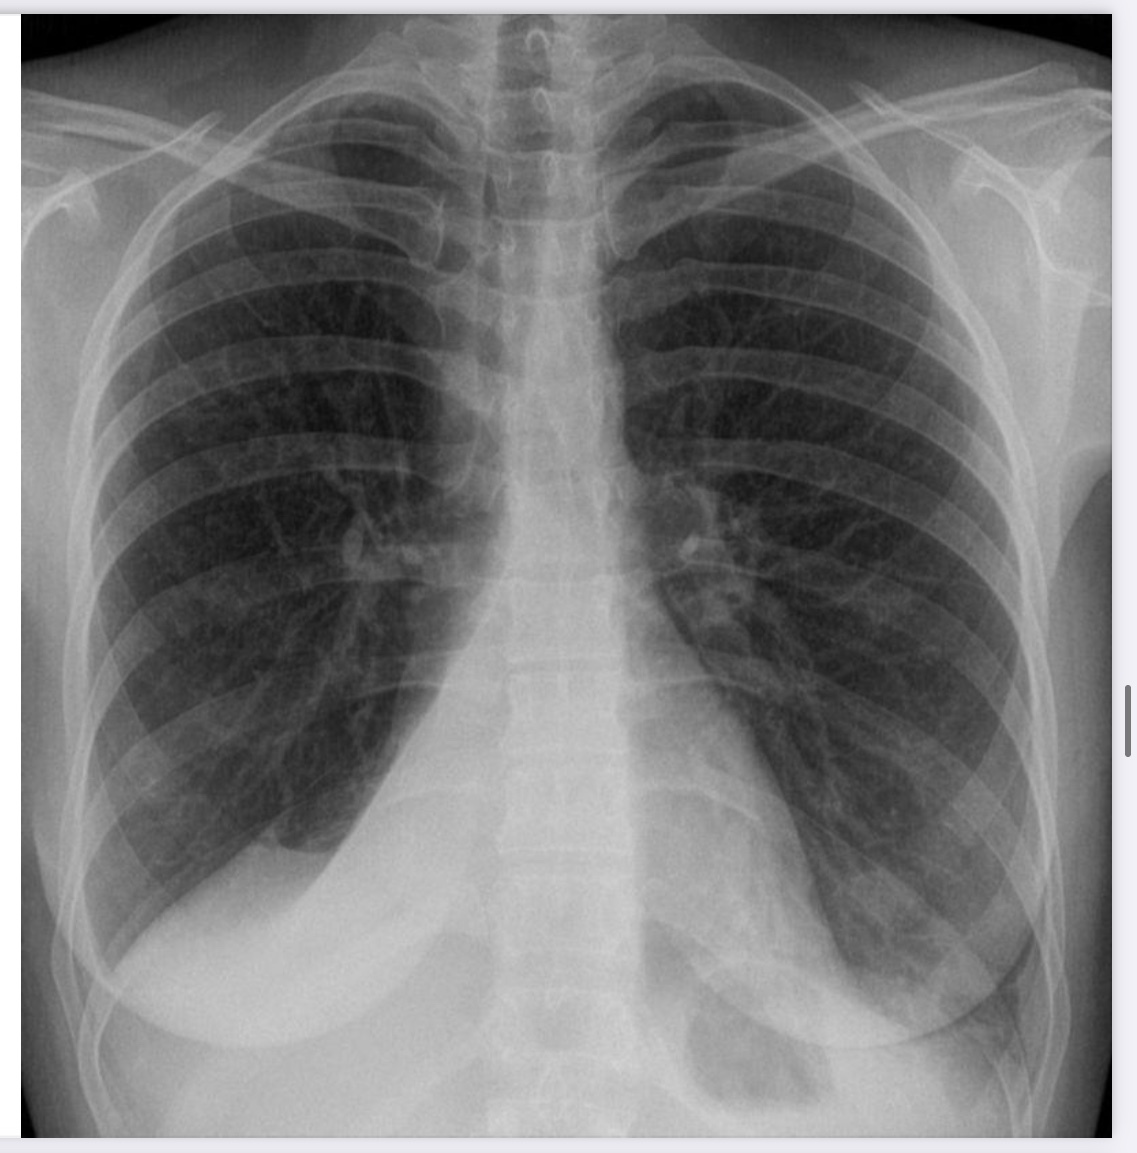

Normal